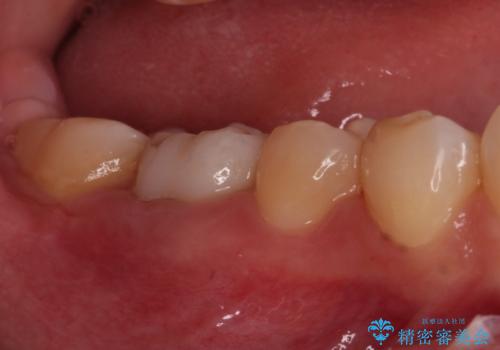

虫歯と抜いたままの奥歯とデコボコの前歯 総合歯科治療

- 放置した虫歯や抜いたままの奥歯、前歯のデコボコを気にして来院された患者様です。

口元の突出感は少なく、下顎の叢生は軽微なものであったので、叢生の強い上顎左右の小臼歯を1本ずつ抜歯し、ワイヤー装置にて矯正治療を行うこととしました。

矯正治療を行う前に、根管治療の必要な上顎前歯と下顎大臼歯の根管治療を行い、矯正治療の途中で下顎の欠損部にインプラント埋入することとし、矯正治療後に補綴治療を行うこととしました。